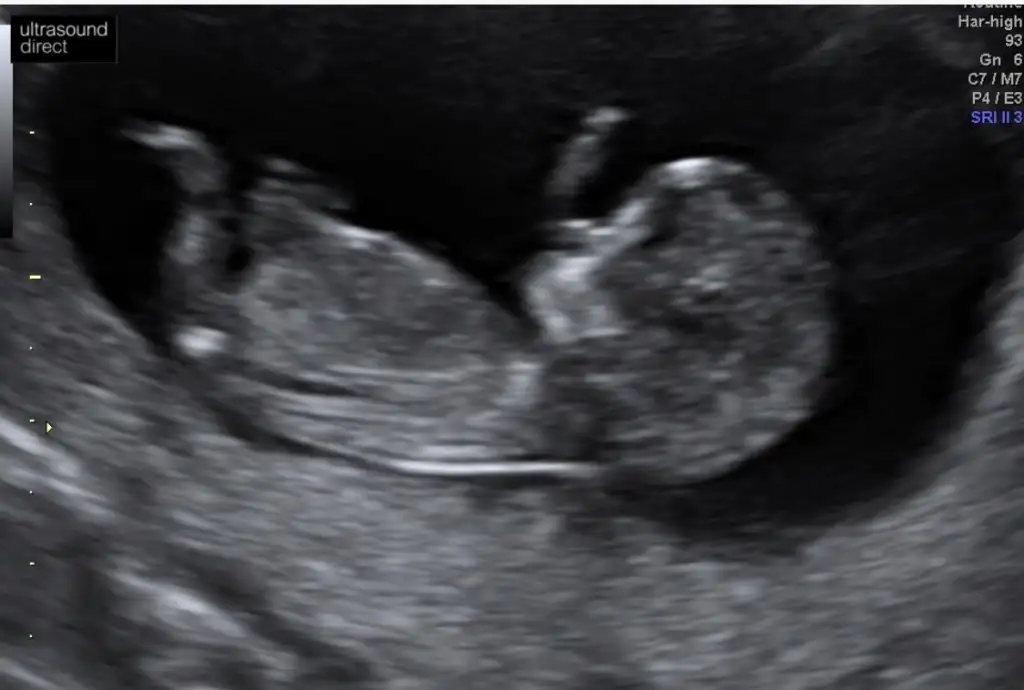

Net degil sanki kız gibi ama kafada erkek şekliDiğerinde hiç net degıldır ama atim Eki Görüntüle 2574696

Daha önce ne dedim bilmiyorum burada nub paralel görünüyor kız gibi 12+ usg olursa paylaşınEki Görüntüle 2574907 Eki Görüntüle 2574908 Eki Görüntüle 2574909 Canım 11+1ız sabah dayanamadık doktora gıttık.cınsıyetı bellı degl ama eşim cok merak edıyor sor bakalım dıyor nub a göre neymıs cınsıyetı dıyebıze tekrar bakarsan cok sevınırım

Daha önce erkek demıstınız ama o zaman 10 haftalıktı.12.haftayı paylaşacağım cok teşekkürlerDaha önce ne dedim bilmiyorum burada nub paralel görünüyor kız gibi 12+ usg olursa paylaşın

11 yada 12 hafta tekrar paylaşırsınız şimdilik erkek ama 12 hafta tahminimi onaylarız

Erkek olduğunu tahmin ediyorum